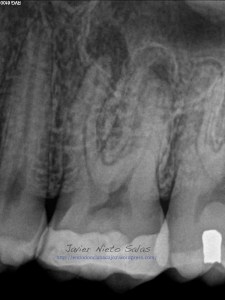

Como podemos ver, en las Rx finales, no afecta el ser conservadores con la estructura dentaria en el tratamiento y resultado final.

Tanto en molares superiores como inferiores